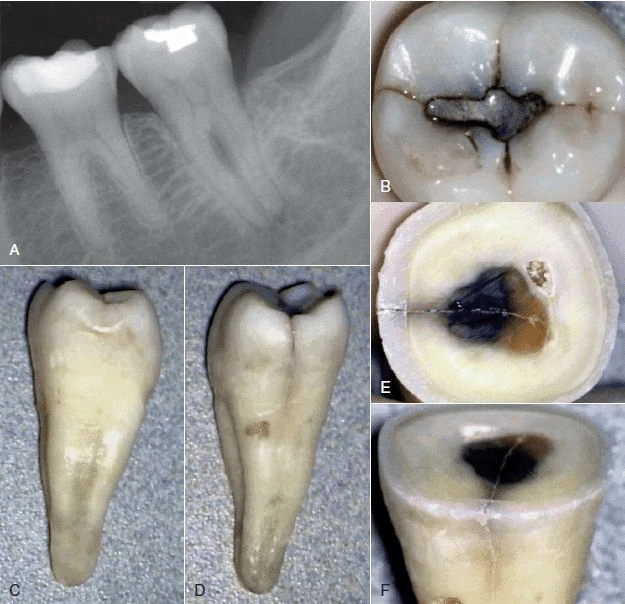

Phương pháp chiếu sáng và dùng thuốc nhuộm

Đôi khi cần phải tháo miếng trám trên răng để có thể quan sát vết nứt rõ hơn. Nhuộm bằng Xanh Methylene bằng cách bôi thuốc lên bề mặt răng bằng đầu tăm bông, thuốc nhuộm sẽ quyên qua vùng nứt và xác định vị trí đường nứt. Chiếu sáng cũng có thể hữu ích hơn bằng cách chiếu trực tiếp ánh sáng có cường độ cao vào bề mặt răng tại đường nối men – xi măng để xem mức độ lan rộng của vết nứt.

Phần răng gần với nguồn sáng sẽ hấp thu ánh sáng và phát sáng, trong khi phần răng phía bên kia của vết nứt không được sánh sáng truyền qua sẽ có màu xám hơn. Mặc dù có thể phát hiện được vết nứt bằng thuốc nhuộm hoặc ánh sáng nhưng độ sâu của vết nứt không thể lúc nào cũng xác định được.

Hình 9. Đôi khi không có dấu hiệu rõ ràng cho thấy lý do răng có triệu chứng. (A) Hình ảnh X quang cho thấy răng cối lớn thứ hai hàm dưới có miếng trám sâu mức độ trung bình. (B) Thử tuỷ cho thấy răng chết tuỷ. Không chiếu sáng nên không thấy có đường nứt nào cả. (C) Chiếu ánh sáng có cường độ cao lên bề mặt răng, quan sát thấy vết nứt ở mặt ngoài. (D) Chiếu sáng vào mặt xa – trong của răng.